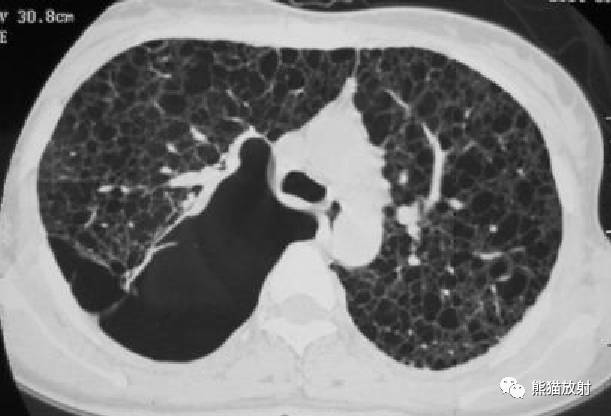

【影像表现】

胸部CT:双肺弥漫分布大小不等薄壁囊状空气密度影,且胸膜下区低密度影明显较其他部位大,周围见索条状高密度影。阴影之间肺组织基本正常。

②双肺弥漫分布囊状空气密度影,有薄壁,小叶中央动脉位于病灶边缘部分。此有别于小叶中央型肺气肿。